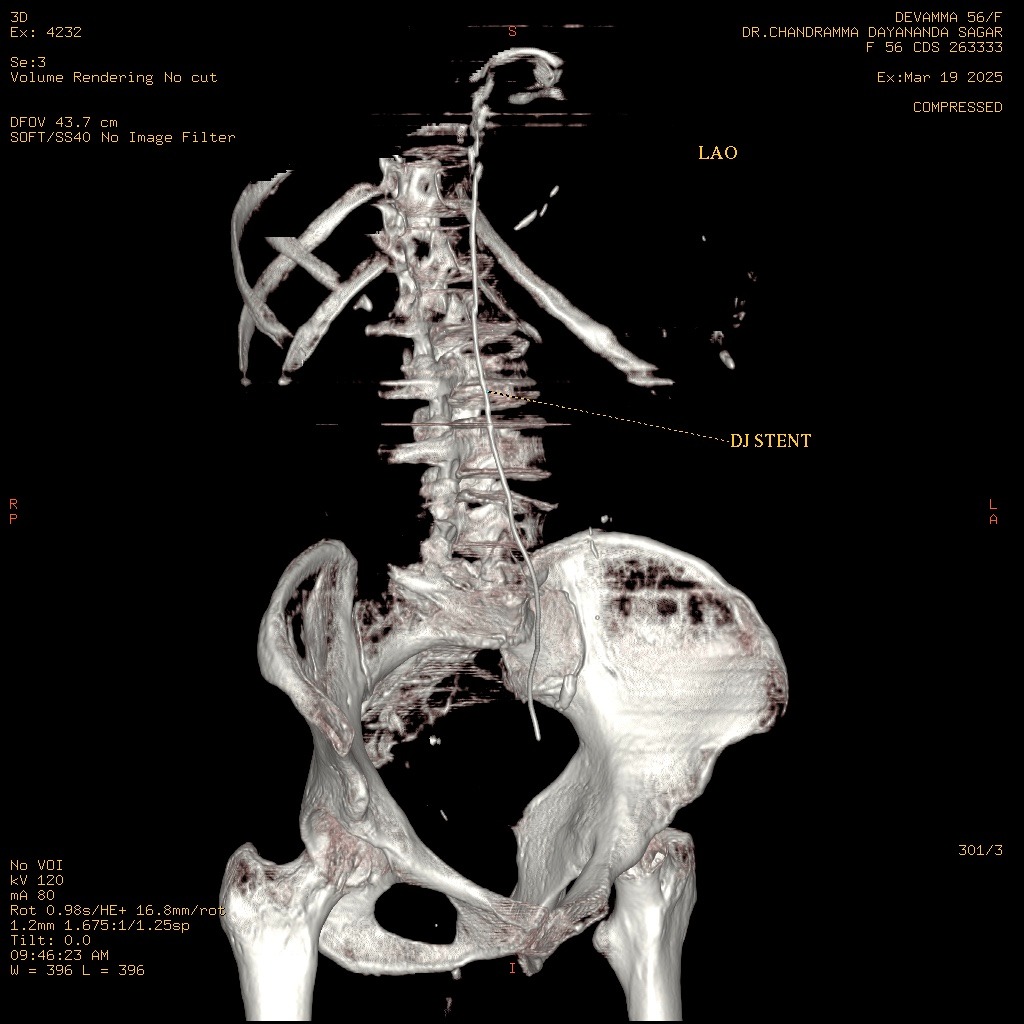

Initial attempts at retrograde left ureteric stenting were hampered by a completely adherent stone, preventing the passage of a standard guide wire. A subsequent thinner, hydrophilic Terumo guide wire was easily negotiated past the obstruction. A diagnostic anomaly was noted when the passage showed an unusual rightward curvature upon successful navigation, leading to suspicion of misplacement.

Following the easy passage of the hydrophilic wire, a 3Fr ureteric stent was passed over it. The stent advanced without resistance, but the proximal pigtail did not coil in the renal pelvis, heightening the suspicion of misplacement. An immediate post-procedure CT scan confirmed the stent's location: the distal end was correctly within the bladder, but the main body and proximal end were located outside the ureter, passing into the Inferior Vena Cava. However, further investigation with MRI of Abdomen revealed that the stent had migrated from the bladder to the left internal iliac vein and reached in the Right Atrium. The patient remained hemodynamically stable. A team meeting was sought, including the opinions of the Cardiologist, Cardiothoracic surgeon, and Urologist, and came to a conclusion that a attempt via endovascular retrieval of the stent. Initial attempts by interventional cardiology via the femoral vein to the Right Atrium failed. Successful retrieval was achieved by an alternative access via the right internal jugular vein, direct entry into the left internal iliac vein. A snare catheter was skillfully deployed to secure the distal end of the DJ stent. The stent was removed successfully without any immediate vascular complication. The patient was monitored in the MICU post-procedure. On the second day post procedure, patient developed mild hematuria and was treated conservatively, and repeat CT KUB with contrast was done, which did not show any remnant fistula.